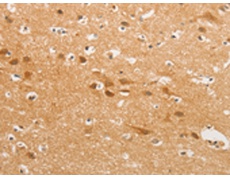

IHC positive control: |

Human brain |

IHC Recommend dilution: |

50-200 |